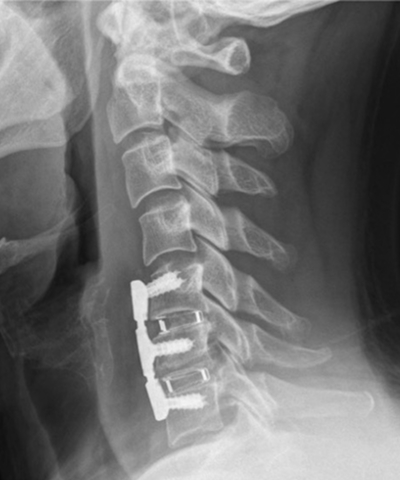

前方除圧固定術

椎間板を摘出し、チタンケージや人工骨で固定

人工椎間板置換術

若年者で可動性を保ちたい場合に適応

当院では顕微鏡下手術を標準化し、切開を最小限にして神経の損傷を防いでいます。